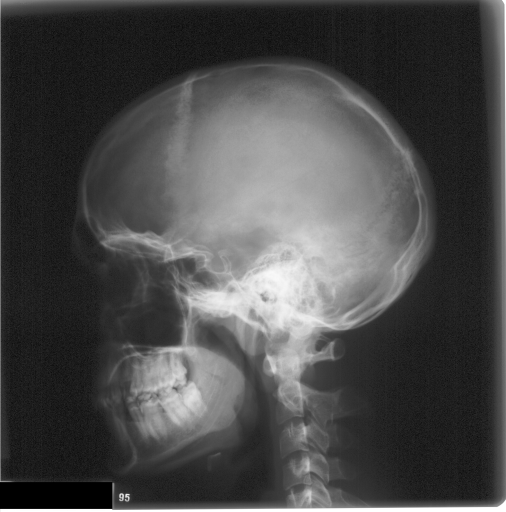

In this section, we report two series of experiments. The first one verifies the correctness or reliability of the micro-DE algorithm to find optimal projections compared to an exhaustive search when we are looking for 4 optimal projection angles out of 16 equidistant angles. In the second experiments, we still provide the results for exhaustive 4/16 selection but examine the evolutionary approach to get 4/180 and 8/180 to investigate the reconstruction accuracy of the micro-DE via correlation of the input image and the reconstructed image using 4/16 (exhaustive), 4/180 (micro-DE) and 8/180 (micro-DE). To conduct the experiments we used 50 images from IRMA dataset [34, 35], a benchmarking collection of 14,400 x-rays images. We selected 10 random classes out of 58 classes, and for each class, we randomly drew 5 images to be used in our experiments. Figure 4 shows the images we have used.

![]() |

[34∘, 79∘, 124∘, 158∘] with |

| [45∘, 79∘, 124∘, 146∘] with | |

[22∘, 67∘, 112∘, 157∘] with |

| [22∘, 56∘, 135∘, 169∘] with | |

[0∘, 79∘, 101∘, 157∘] with |

| [0∘, 68∘, 112∘, 169∘] with | |

[22∘, 68∘, 124∘, 157∘] with |

| [22∘, 68,∘,135,∘, 169∘] with |

In this series of experiments, we randomly selected three categories from IRMA dataset (namely, breast, foot and lung), and for each category we choose 5 random images from that class (Figures 5, 6 and 7 show these images). When we find “4 out of 180” (4/180) and “8 out of 180” (8/180) projections via micro-DE (tasks that cannot be performed via brute-force), then the question is what can we say about the reconstruction error, in terms of correlation between original and reconstructed images, when we compare evolutionary approximation with the case that we can manage via exhaustive search, namely “4 out of 16” (4/16)? Can micro-DE reach at least the same correlation (similarity) as the brute-force case in lower dimensions? If yes, we may have more confidence in using micro-DE in practice where we cannot apply brute force for benchmarking or direct use, especially for higher dimensions (i.e., the number of projections).